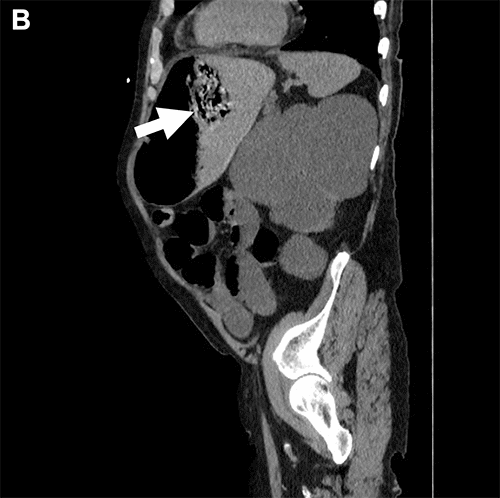

At the initial examination, the patient was alert, oriented, and complaining of severe abdominal pain. He was hypertensive with otherwise normal vital signs and a body mass index of 22. His abdomen was distended, tympanic, and diffusely tender. His laboratory tests included a white blood cell count of 14,400 per µL, a serum bicarbonate of 15 mEq/L, and a serum lactate of 6 mmol/L. Attempts at nasogastric tube placement were unsuccessful secondary to resistance during insertion. A computerized tomography (CT) scan obtained in the emergency department demonstrated (i) markedly dilated loops of small bowel with a transition point in the distal ileum, (ii) portal venous gas, (iii) a small ventral hernia containing a non-obstructed loop of colon, and (iv) a foreign body (possibly a bezoar) freely floating within the lumen of a distended, intraabdominal stomach (Figure 1).

Figure 1. Preoperative CT. Published with Permission

A) Cross-sectional view, upper abdomen. Large arrow = free-floating mass within lumen of stomach. Small arrows = portal venous gas

B) Sagittal view, left side

C) Coronal view, anterior